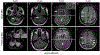

Aquaporin-4-IgG positive neuromyelitis optica spectrum disorder (AQP4+NMOSD) and myelin-oligodendrocyte glycoprotein antibody-associated disease (MOGAD) are antibody-associated diseases targeting astrocytes and oligodendrocytes, respectively. Their recognition as distinct entities has led to each having its own diagnostic criteria that require a combination of clinical, serologic, and MRI features. The therapeutic approach to acute attacks in AQP4+NMOSD and MOGAD is similar. There is now class 1 evidence to support attack-prevention medications for AQP4+NMOSD. MOGAD lacks proven treatments although clinical trials are now underway. In this review, we will outline similarities and differences between AQP4+NMOSD and MOGAD in terms of diagnosis and treatment.